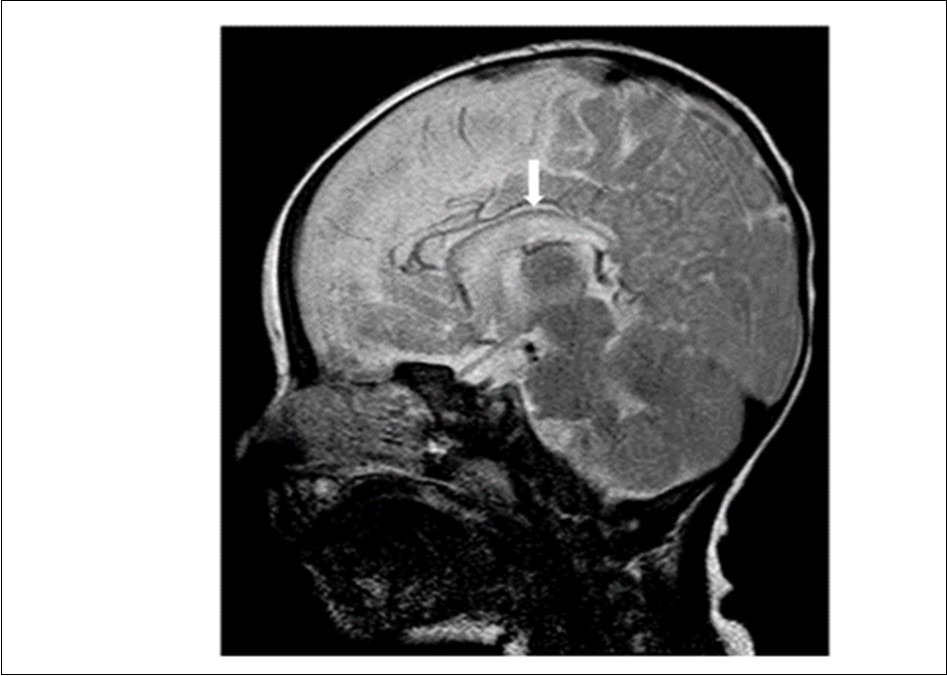

Cranial magnetic resonance imaging (MRI) was requested owing to the patient’s convulsion history and retarded development. The cranial MRI showed diffuse hypoplasia of the corpus callosum in the midline sagittal T2-weighted image (Figure 1 white arrow). T1-weighted imaging showed hypointensity due to delayed myelination of the genu of the corpus callosum (Figure 2, white arrow), which should normally appear hyperintense like the posterior limb of the internal capsule (Figure 2, blue arrow).

Figure 1.Midline sagittal T2-weighted magnetic resonance image of the patient showing diffuse hypoplasia of the corpus callosum.